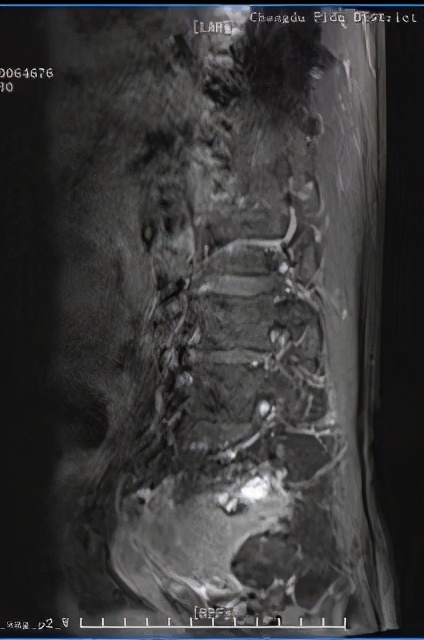

术前CT及MRI检查发现腰5/骶1椎管及左侧神经根管、椎旁软组织肿块

经过术前的检查和邓主任丰富的临床经验,使诊断渐趋明朗, 邹大爷的肿瘤需要进行手术切除,任其发展会产生严重的后果。